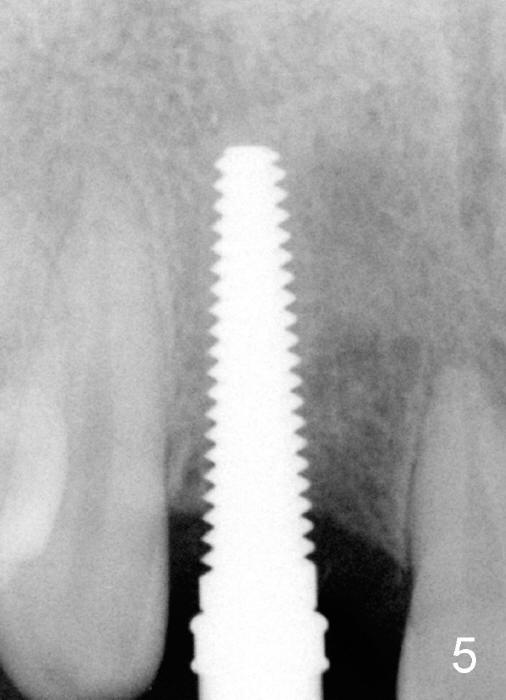

Malpositioned implant in the anterior region is cosmetically unacceptable. Immediate provisional allows us to note the issue immediately. The crown looks too long. Secondly, the provisional is easily dislodged, since the buccal aspect of the angled abutment is over trimmed (Fig.1). The implant (3.8x14 mm), which has been placed 3.5 months, is unexpectedly easily removed by reverse torque (Fig.2). The buccal wall is intact, whereas there seems to be enough bone lingually to place an implant. A small incision is made (Fig.11) so that the gingival tissue can be transferred buccally (Fig.12) and the immediate implant is to be placed palatally (Fig.13 white circle). There is no difficulty forming osteotomy in the palatal wall, followed by inserting 4.5x20 mm tap at the depth of 17 mm (Fig.3,5). But the tap is not palatal enough (Fig.4). By removing more palatal bone, the 4.5x17 implant (Fig.6) appears to be placed palatally enough for restoration (Fig.7; A: abutment; *: buccal gap). The biggest problem is that the palatal flap (Fig.7 arrowheads) cannot be pushed buccally; instead remains palatally. This leads to buccal tissue deficiency (Fig.8). Connective tissue graft is offered, but declined. The patient insists that she has low smile line. Following immediate provisional, mixture of allograft and synthetic graft is placed in the buccal gap (Fig.9). The overbuilt graft is held in place by perio dressing.